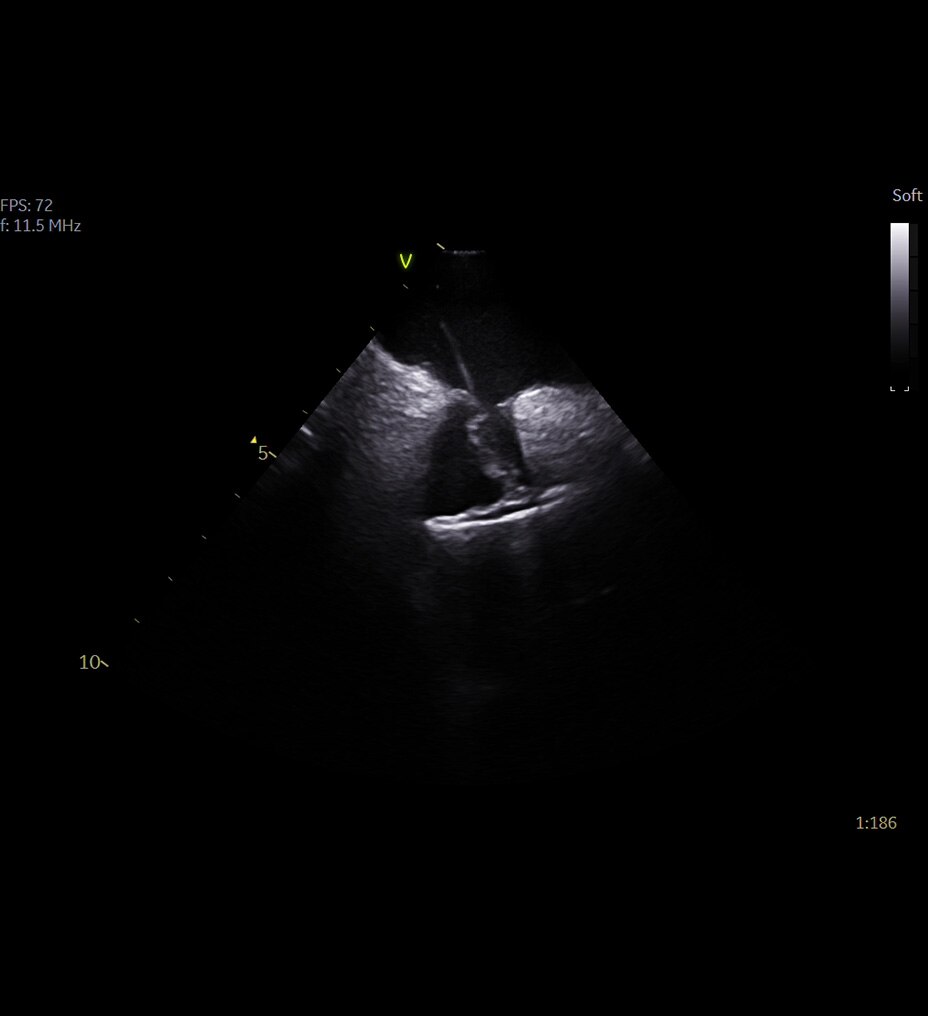

Mejore sus capacidades de diagnóstico con la innovadora cadena de adquisición de imágenes de Clarity, así como la calidad de sus imágenes en hasta un 30 %*

Cadena de adquisición de imágenes innovadora: la cadena de adquisición de imágenes de Clarity está formada por el detector del panel Atlas, el tubo de rayos X, el generador compacto de alta tensión y, de forma opcional, la reconstrucción ASiR. Ofrece una gran resolución espacial con ruido bajo y menos artefactos para satisfacer las diversas necesidades de los clientes en situaciones clínicas reales.